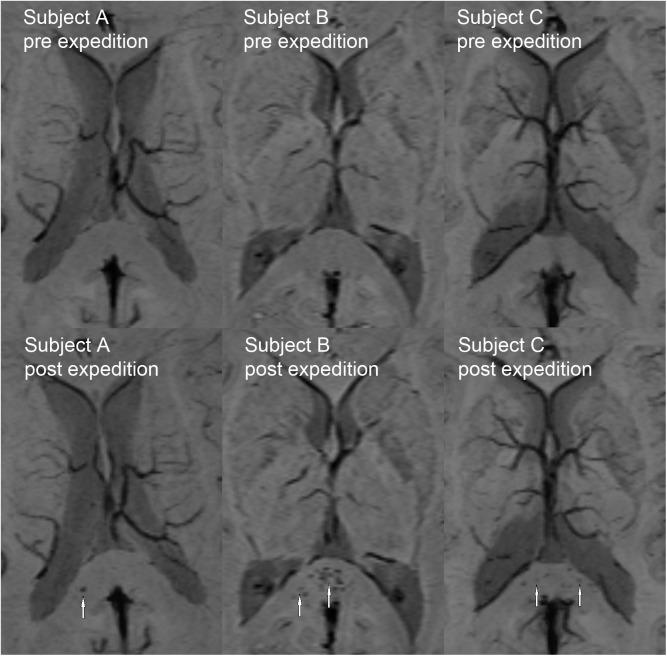

On post-expedition imaging no new white matter hyperintensities were observed. Compared to baseline testing, we observed a significant cerebrospinal fluid fraction increase (0.34% [95% CI 0.10-0.58], p = 0.006) and a white matter fraction reduction (-0.18% [95% CI -0.32--0.04], p = 0.012), whereas the grey matter fraction remained stable (0.16% [95% CI -0.46-0.13], p = 0.278). Post-expedition imaging revealed new microhemorrhages in 3 of 15 climbers reaching an altitude of over 7000 m. Affected climbers had significantly lower oxygen saturation values but not higher acute mountain sickness scores than climbers without microhemorrhages.

探险后成像未观察到新的白质高信号。与基线测试相比,我们观察到脑脊液分数显著增加(0.34% [95%置信区间0.10 - 0.58],p = 0.006)和白质分数降低(-0.18% [95%置信区间-0.32 - -0.04],p = 0.012),而灰质分数保持稳定(0.16% [95%置信区间-0.46 - 0.13],p = 0.278)。探险后成像显示,在15名攀登超过7000米海拔高度的登山者中,有3人出现了新的微出血。与没有微出血的登山者相比,受影响的登山者的血氧饱和度值显著更低,但急性高山病评分并未更高。